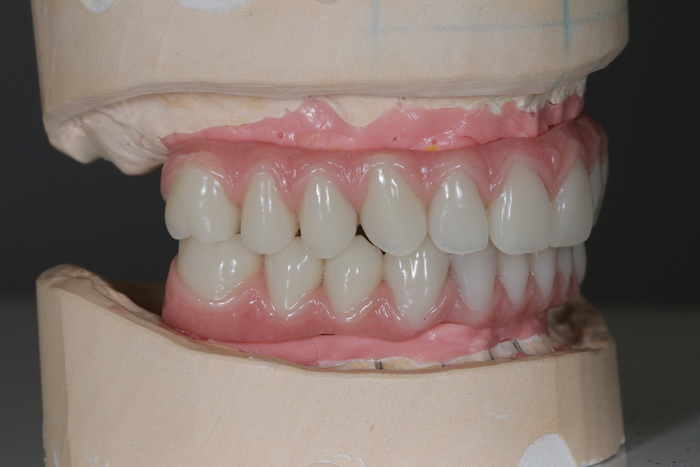

Далее ортопедом были сняты слепки, а техник в лаборатории изготовил вот такой постоянный протез с опорой на имплантатах.

И, наконец, вот так выглядит протез в полости рта